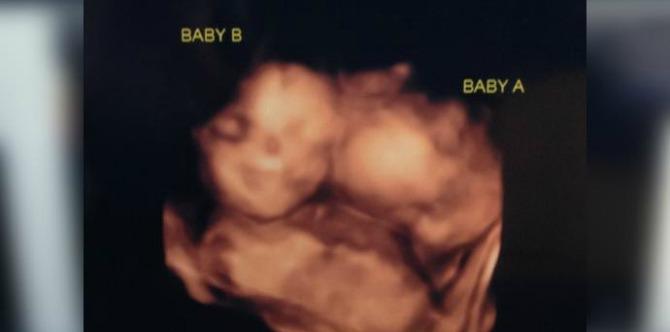

During the couple’s first pregnancy checkup they found out that they’re awaiting a rare set of ‘MoMo’ twins, a case in which the babies share the same placenta and amniotic sac.

“He almost fainted,” Jessica says in an ABC 8 report. “We were just staring at the screen and we were like, ‘there are two heads in there!’”

Photo credit: ABC